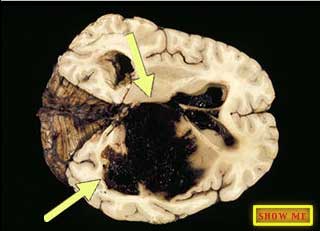

Can you see the areas that are filled with blood?